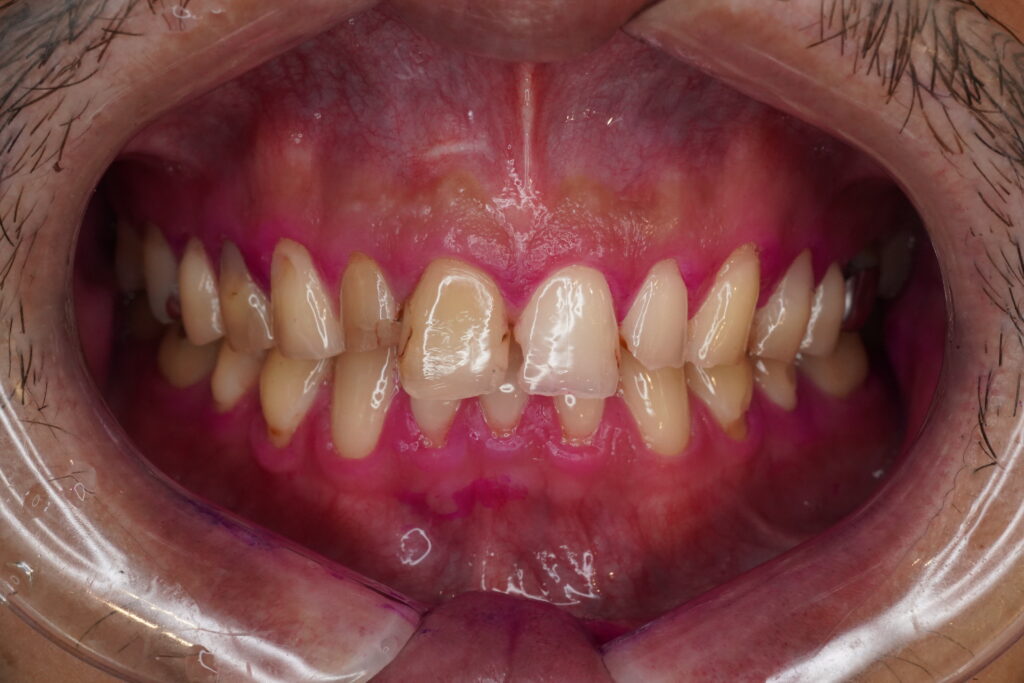

【患者様】 👨 30代

【主訴】

7-8年前に前歯に詰めたプラスチックが欠けたので治してほしい。

【治療計画】

元々の前歯の長さが不揃いであったり、他部位に詰めてあるプラスチックが劣化してきている箇所があったため、前歯4本での修復となりました。

【処置前】